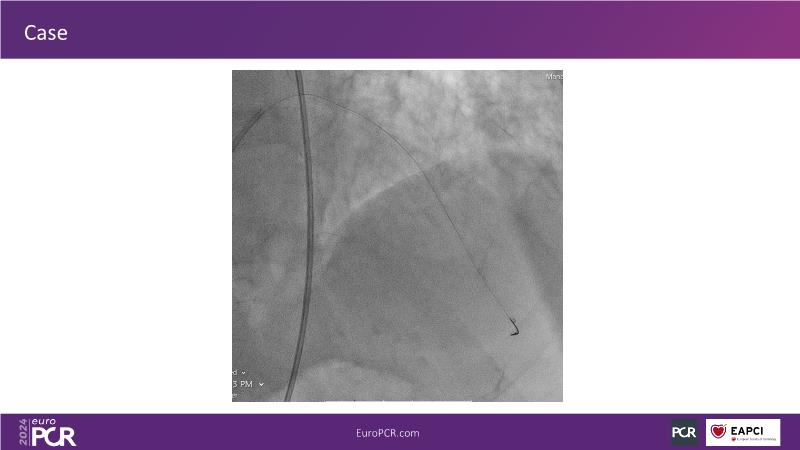

Tune into this 2024 session for insights into the latest ESC guidelines, strategies to prevent and treat no reflow, and an examination of trials like TASTE, TAPAS, and TOTAL on coronary thrombus management. Explore also the outcomes of the CHEETAH study, pondering a potential paradigm shift, and delve into a case study on thrombus removal in a patient with high thrombus burden.